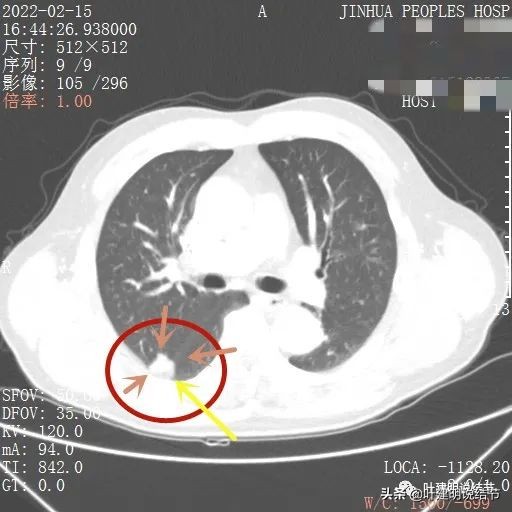

我们先来看下他的CT平扫5毫米层厚的图像:

病灶出现,有血管进入(桔色箭头),有轻微胸膜牵拉(蓝色箭头)

病灶基本实性,但边缘稍不平整,有的边比较平直,但仍是不光滑的